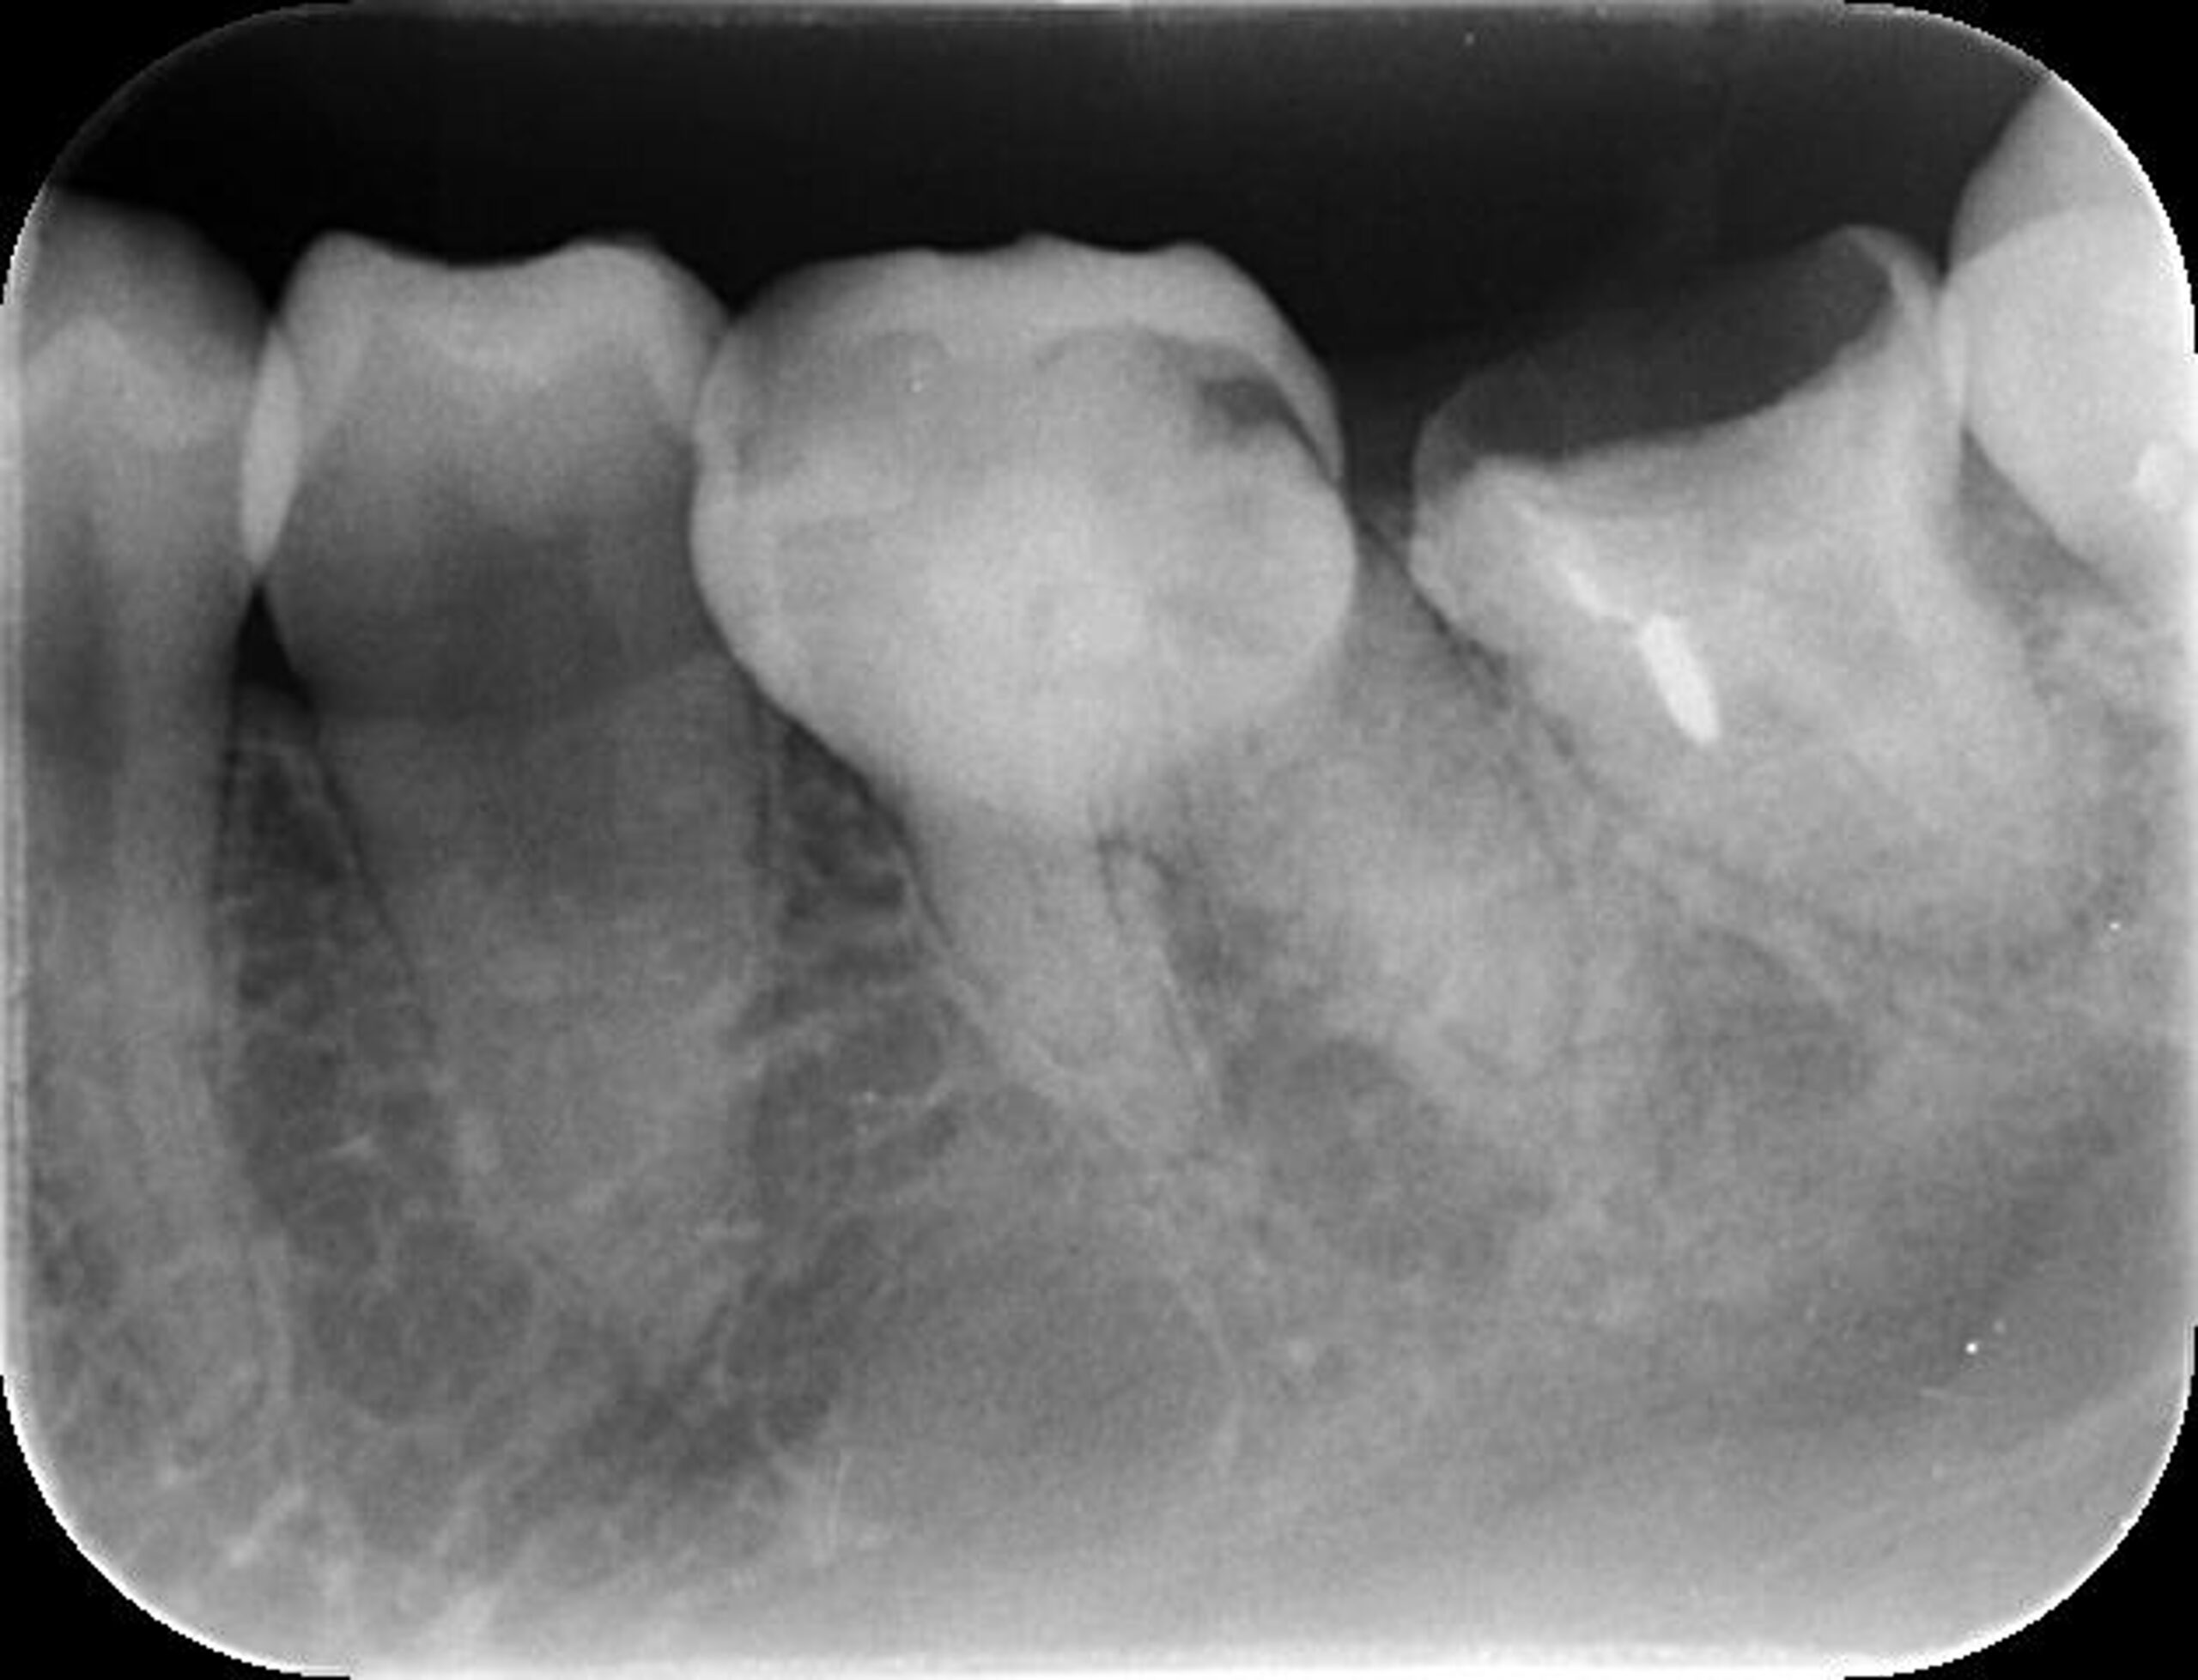

| 来院時の主訴 | 「左下の歯グキが腫れてきた。」 |

| 医院の診断 | 慢性根尖性歯周炎、歯根破折 |